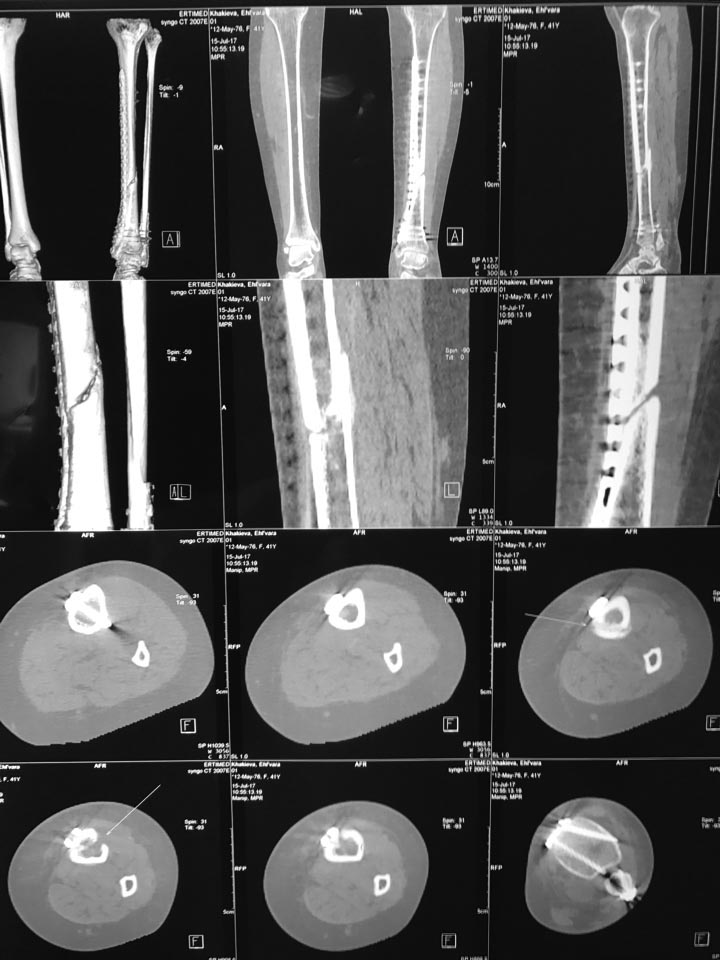

КТ выполнено, прилагаю фото.

Насчет остеосинтеза малоберцовой, выполнен остеосинтез косого перелома

стягивающим винтом, с противоскользящей(опорной)функцией фиксирована 1/3

трубчатой пластиной.

А что именно смущает? Расположение пластины по задне-наружной

поверхности? Отсутствие винтов в дистальном отломке? или что то другое?

В общем, с малоберцовой проблем вроде нет.